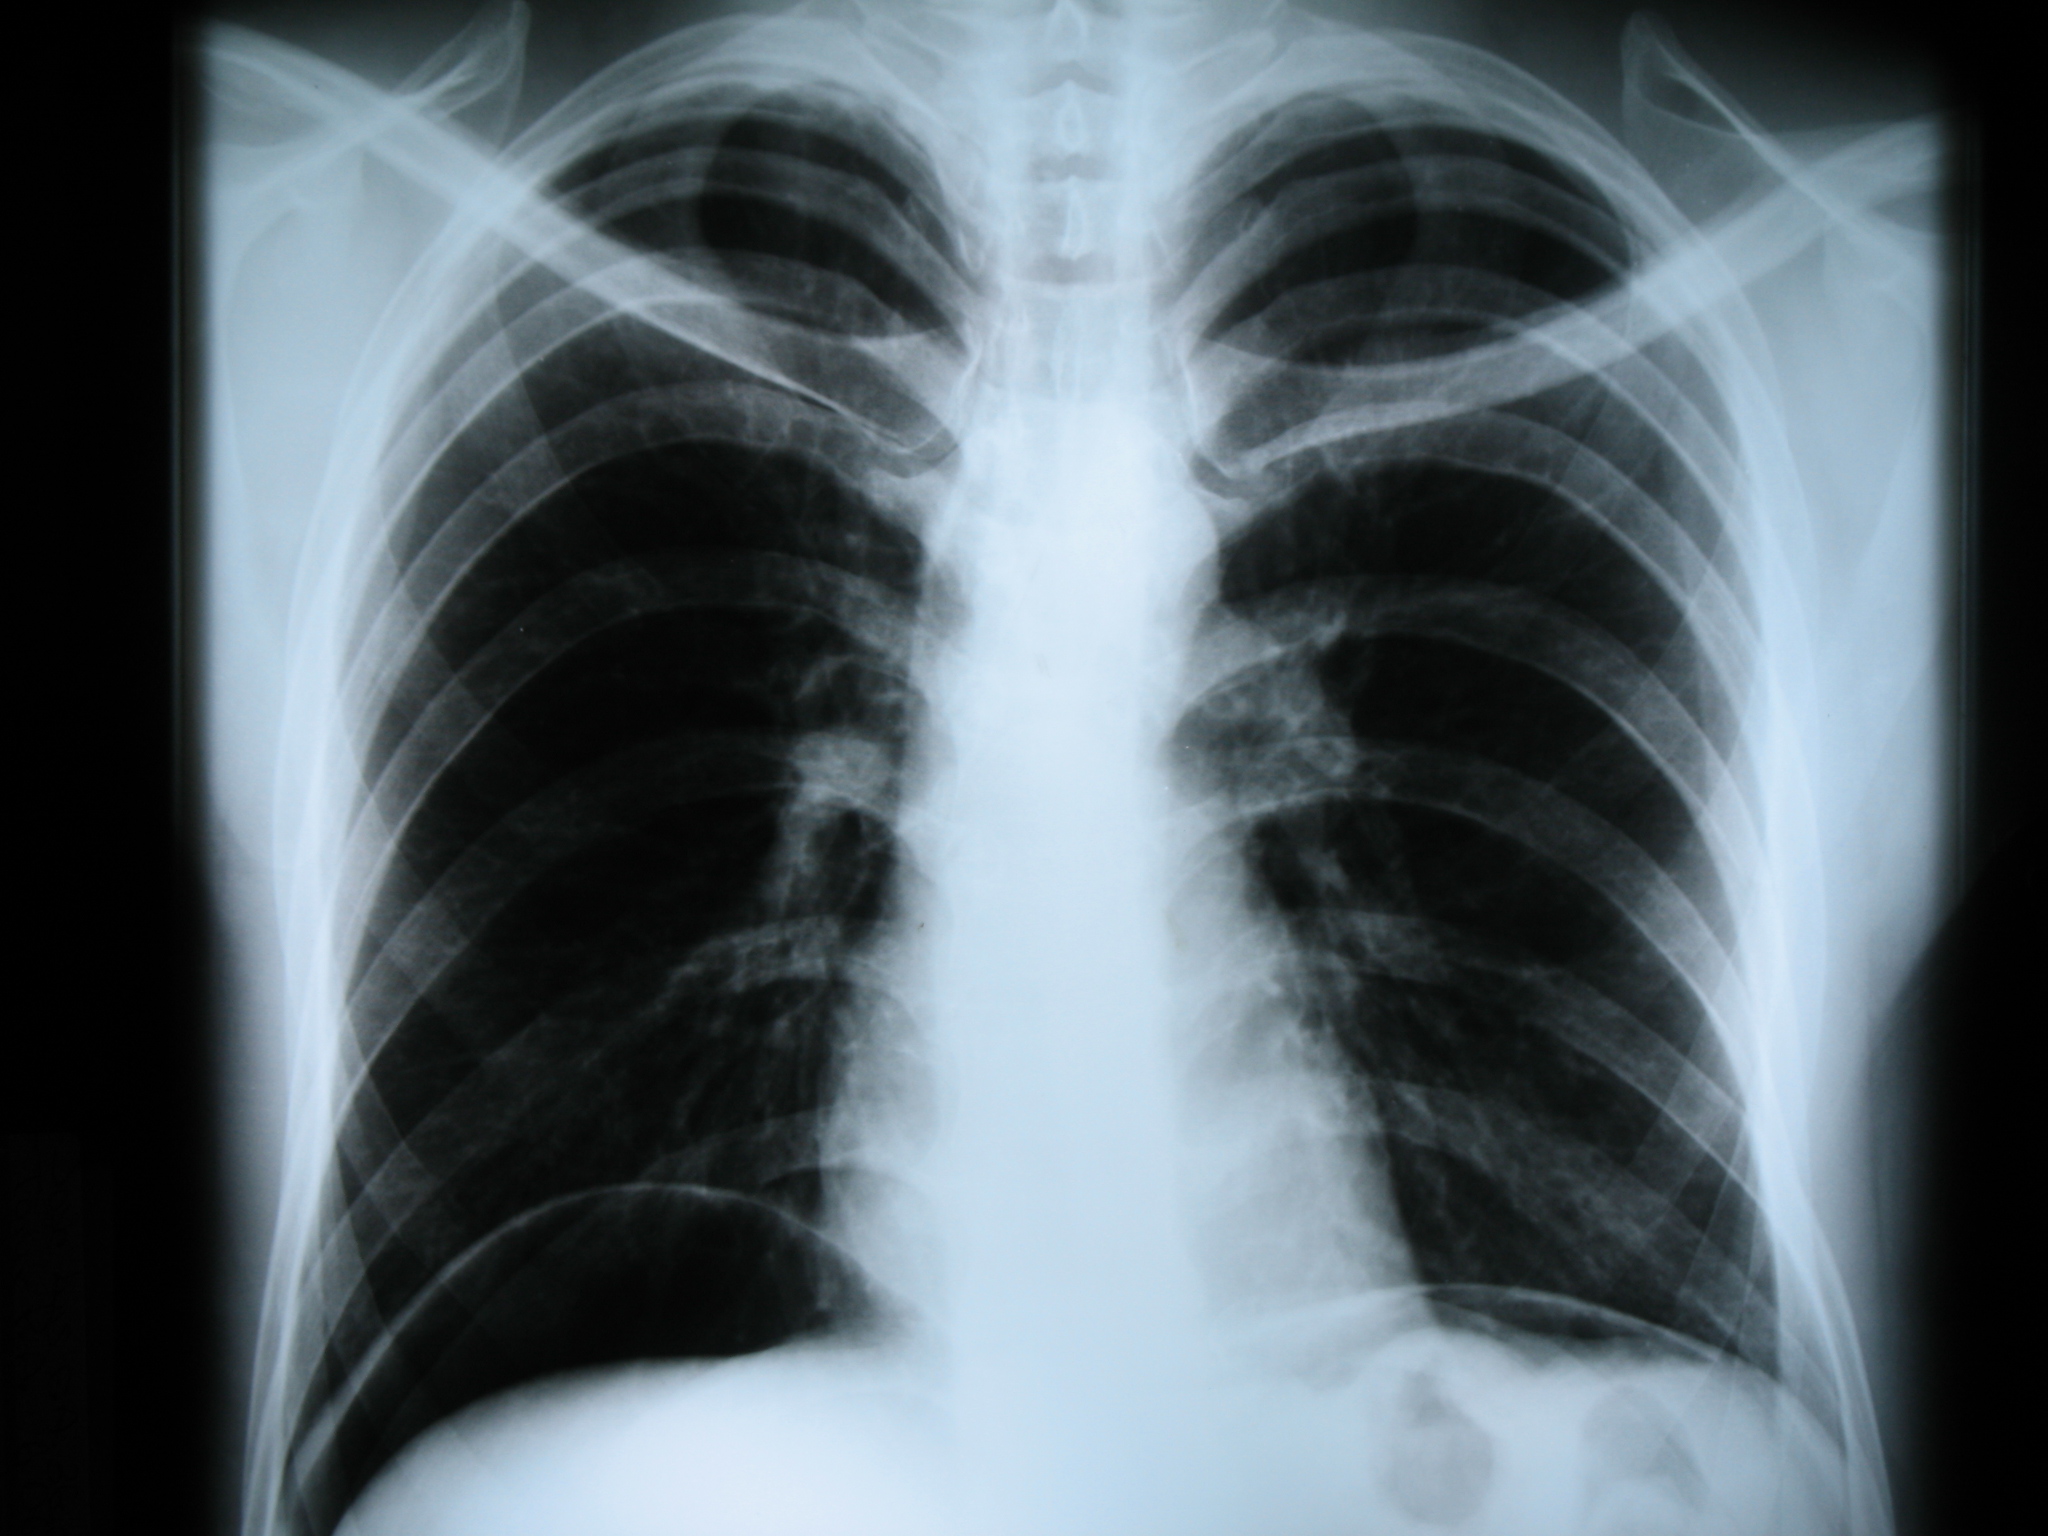

Диагностика

Когда женщины испытывают боли в области сердца, они чаще всего обращаются к терапевту или кардиологу. В зависимости от истории болезни и сопутствующих симптомов, диагностику и лечение могут проводить гастроэнтерологи, неврологи или пульмонологи. Для установления точного диагноза могут потребоваться следующие анализы и исследования:

- рентгенография;